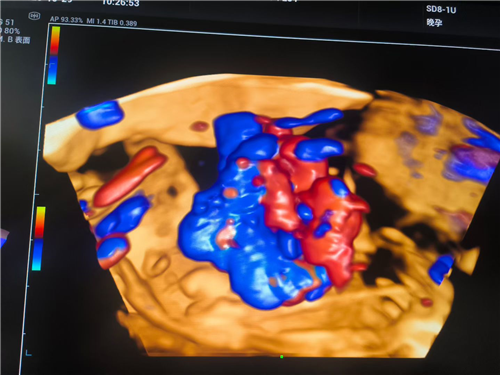

近日,一名既往有脊柱手术史的孕35周孕妇就诊妇产科门诊,因产检胎监突现异常信号,常驻我院的上海国际和平妇幼保健院黄鼎副院长带领妇产科团队迅速会诊,B超室主任联合上海专家确诊“脐带真结”,并已导致胎儿胎心下降。医院立即启动顶级应急响应,麻醉科、妇产科、新生儿科等团队采用全麻下紧急剖宫产方案,3小时完成从诊断到分娩的生命接力。

我院即将启动麻醉疼痛门诊,将为手术患者提供术前评估服务,进一步优化手术流程,提升手术安全性,为患者提供更全面的医疗保障。我院超声科在依托“上海常驻专家+本土优秀团队”的双优模式,在核心诊疗领域形成显著竞争力,尤其在产前筛查方面,凭借专业实力为母婴健康保驾护航。